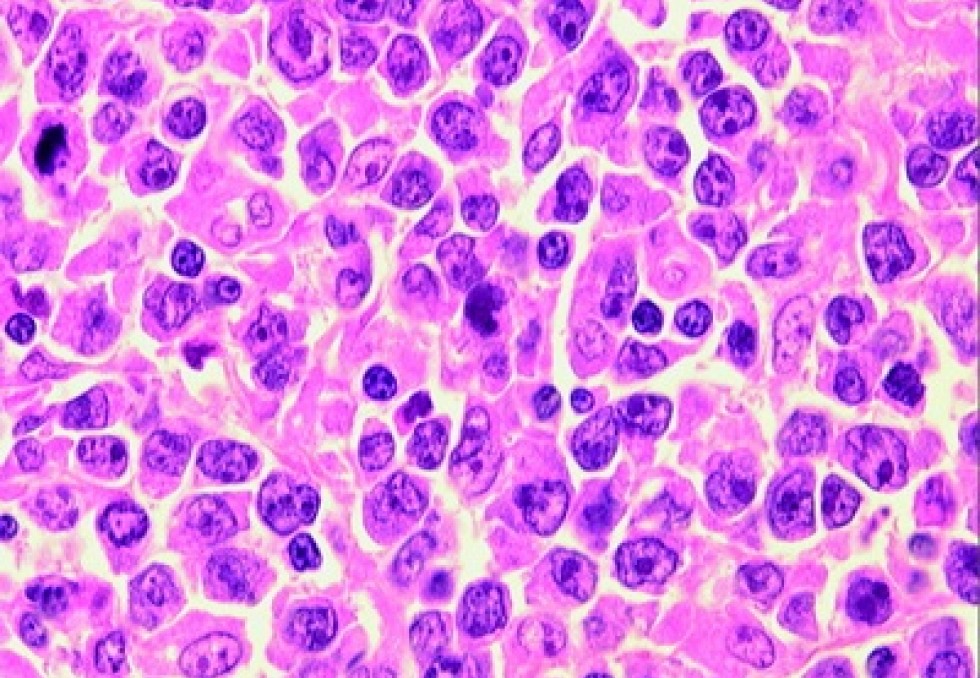

C’est ainsi que des cas de guérison ont pu être observés dans des situations a priori très défavorables, le cas le plus spectaculaire car le plus médiatisé étant celui de l’ancien Président des Etats-Unis Jimmy Carter, traité par immunothérapie pour un mélanome métastasé au cerveau et aujourd’hui en rémission, voire guéri. Mais les anticorps monoclonaux ne sont pas la seule piste, une autre émerge et semble très prometteuse, celle des cellules CAR-T. L’idée est d’utiliser des lymphocytes T provenant d’un donneur sain ou du patient lui-même, lymphocytes T qui grâce à l’ingénierie cellulaire vont exprimer des récepteurs chimériques antigéniques (CARs ou Chimeric Antigen Receptors) reconnaissant un antigène spécifique exprimé par des cellules malignes. Après amplification, ces cellules CAR-T sont donc réinjectées au patient. Cette technologie est notamment la signature de Cellectis, une biotech française issue de l’Institut Pasteur, cotée à Paris et New York, spécialisée depuis plusieurs années dans le développement des CAR-T, notamment dans le traitement des hémopathies malignes, en particulier les leucémies lymphoblastiques aiguës ou les leucémies lymphoïdes chroniques. En 2015, une première patiente en bas âge avait guéri après traitement avec le produit UCART19. En mai 2016, lors de la conférence annuelle de l'American Society of Gene & Cell Therapy (ASGCT), Cellectis avait annoncé la rémission d'un deuxième très jeune enfant atteint de leucémie agressive grâce à cette technologie fondée sur des cellules CAR-T allogéniques ingénieriées. Dans les deux cas, le traitement avait été utilisé dans le cadre d’un usage compassionnel, sachant que l’issue aurait été rapidement fatale en l’absence de traitement efficace. Lors du 59e congrès annuel de l'American Society of Hematology (ASH), qui se déroulera à Atlanta (Etats-Unis) du 9 au 12 décembre, plusieurs communications seront consacrées aux candidats-médicaments CAR-T de Cellectis, en particulier UCART19 dont les droits exclusifs ont été acquis par Servier et qui est codéveloppé par Servier et Pfizer. On peut signaler d’ores et déjà les résultats favorables de deux études de phase 1 menées dans le traitement des leucémies lymphoblastiques aiguës (LLA) à cellules B CD19-positives, en rechute ou réfractaires.